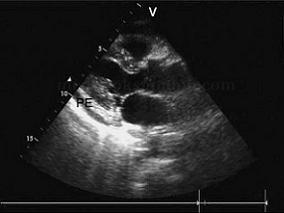

1小时条评论病史和相关检查 患者,女性,44岁。反复咳嗽、低热5年余,呼吸困难、腹胀、下肢水肿10天来诊。 查体:慢性病容,双肺可闻及湿性啰音,心脏浊音界向两侧扩大,心尖搏动弱,心音低而遥远,颈静脉怒张,肝大,腹水,下肢轻度水肿。 超声图片 如图2‐1‐220。 图2...